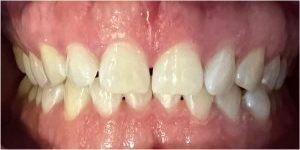

zwężone łuki zębowe,

tyłozgryz,

głęboki zgryz,

stłoczenia,

zrotowane i starte zęby

Pod opieką Agnieszki Łukowicz, Master of Science Orthodontics została poddana zaawansowanemu leczeniu aparatem stałym ligaturowym, Dzięki czemu udało się osiągnąć znaczące zmiany:

poszerzenie luków zębowych,

korekta tyłozgryzu,

rozwiązanie stłoczenia,

odrotowanie zrotowanych zębów,

odbudowa startych zębów.

Efekt estetyczny został dopełniony przez wybielanie zębów i odbudowę kompozytową wykonaną przez dr Monikę Niewitecką.

Przedstawiamy piękny i zdrowy uśmiech naszej Pacjentki!